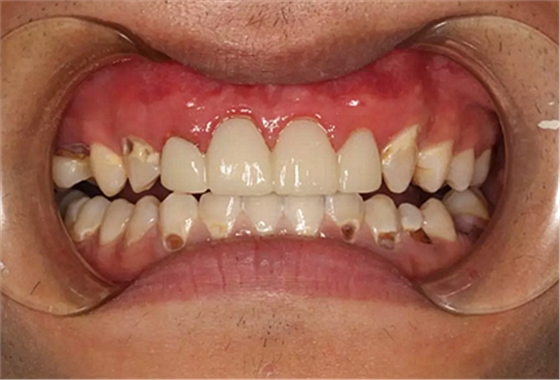

現(xiàn)在剩下的任務(wù)就是為我其他的兄弟姐妹們治療了。需要做根管的做根管,需要做冠的做冠,需要樹脂充填的做樹脂充填。前前后后主人帶我們進(jìn)行了12次的復(fù)診,歷時(shí)6個(gè)月,現(xiàn)在的我們是這樣的

再來看看曾經(jīng)的我們

經(jīng)歷了如此長(zhǎng)久的治療,主人應(yīng)該也是吸取了教訓(xùn),或許以后會(huì)改了不良的生活習(xí)慣,而我們經(jīng)歷了這段涅槃之旅,雖然也煥然一新,重塑了容顏,卻也是歷經(jīng)辛苦,如果主人能好好待我們,其實(shí)這樣的痛苦本不需要經(jīng)歷。

愿我們都能被自己的主人溫柔以待,及時(shí)給我們做體檢,讓我們能為自己的主人服務(wù)的更長(zhǎng)久。